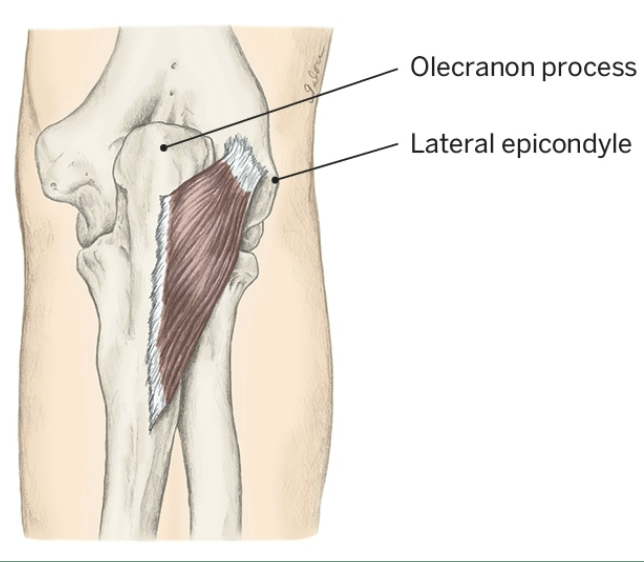

Action of Anconeus

Elbow Extension

Origin of Anconeus

Lateral epicondyle

Insertion of Anconeus

Olecronon process and posterior, proximal ulna

Nerve that the Anconeus innervates